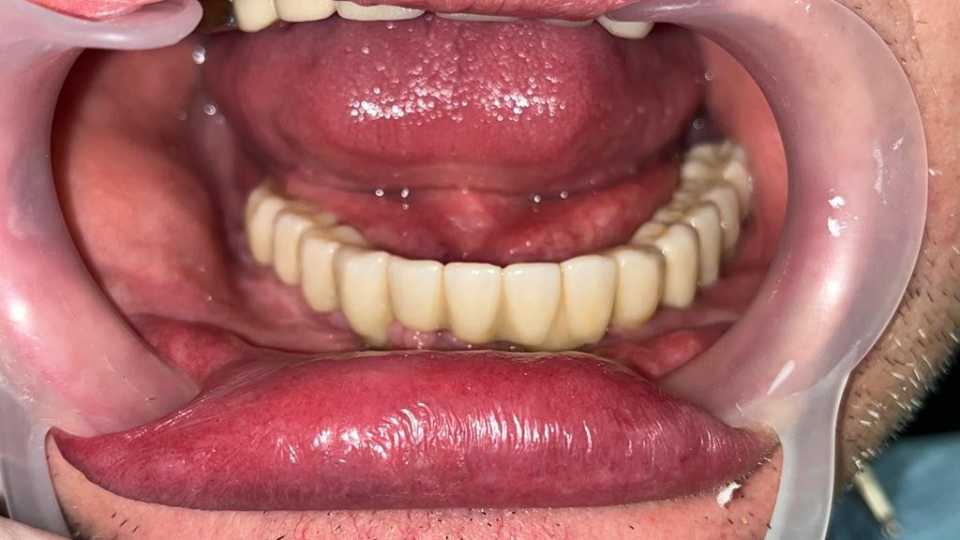

Lucrare fixă înșurubabilă pe implanturi

Cazul 53: All on 6

Pacient în vârstă de 45 de ani, vechi purtator de proteza totală inferioara s a prezentat cu dorința de a efectua o lucrare pe implanturi fixa.

Cazul a fost unul foarte dificil prin prisma resorbtiei osoase în zonele laterale mandibulare și ale patologiilor asociate ale pacientului, prohibitive pentru adiții osoase.

Astfel, am optat, impreuna cu pacientul, pentru 6 implanturi Straumann BLX Roxolid, inserate lateral de nervul alveolar inferior, metodă care ne-a ajutat sa evitam procedura de aditie osoasă, pe care am realizat o lucrare fixa insurubabila din Zirconiu.

Rezultatul final a fost pe masura așteptărilor pacientului.